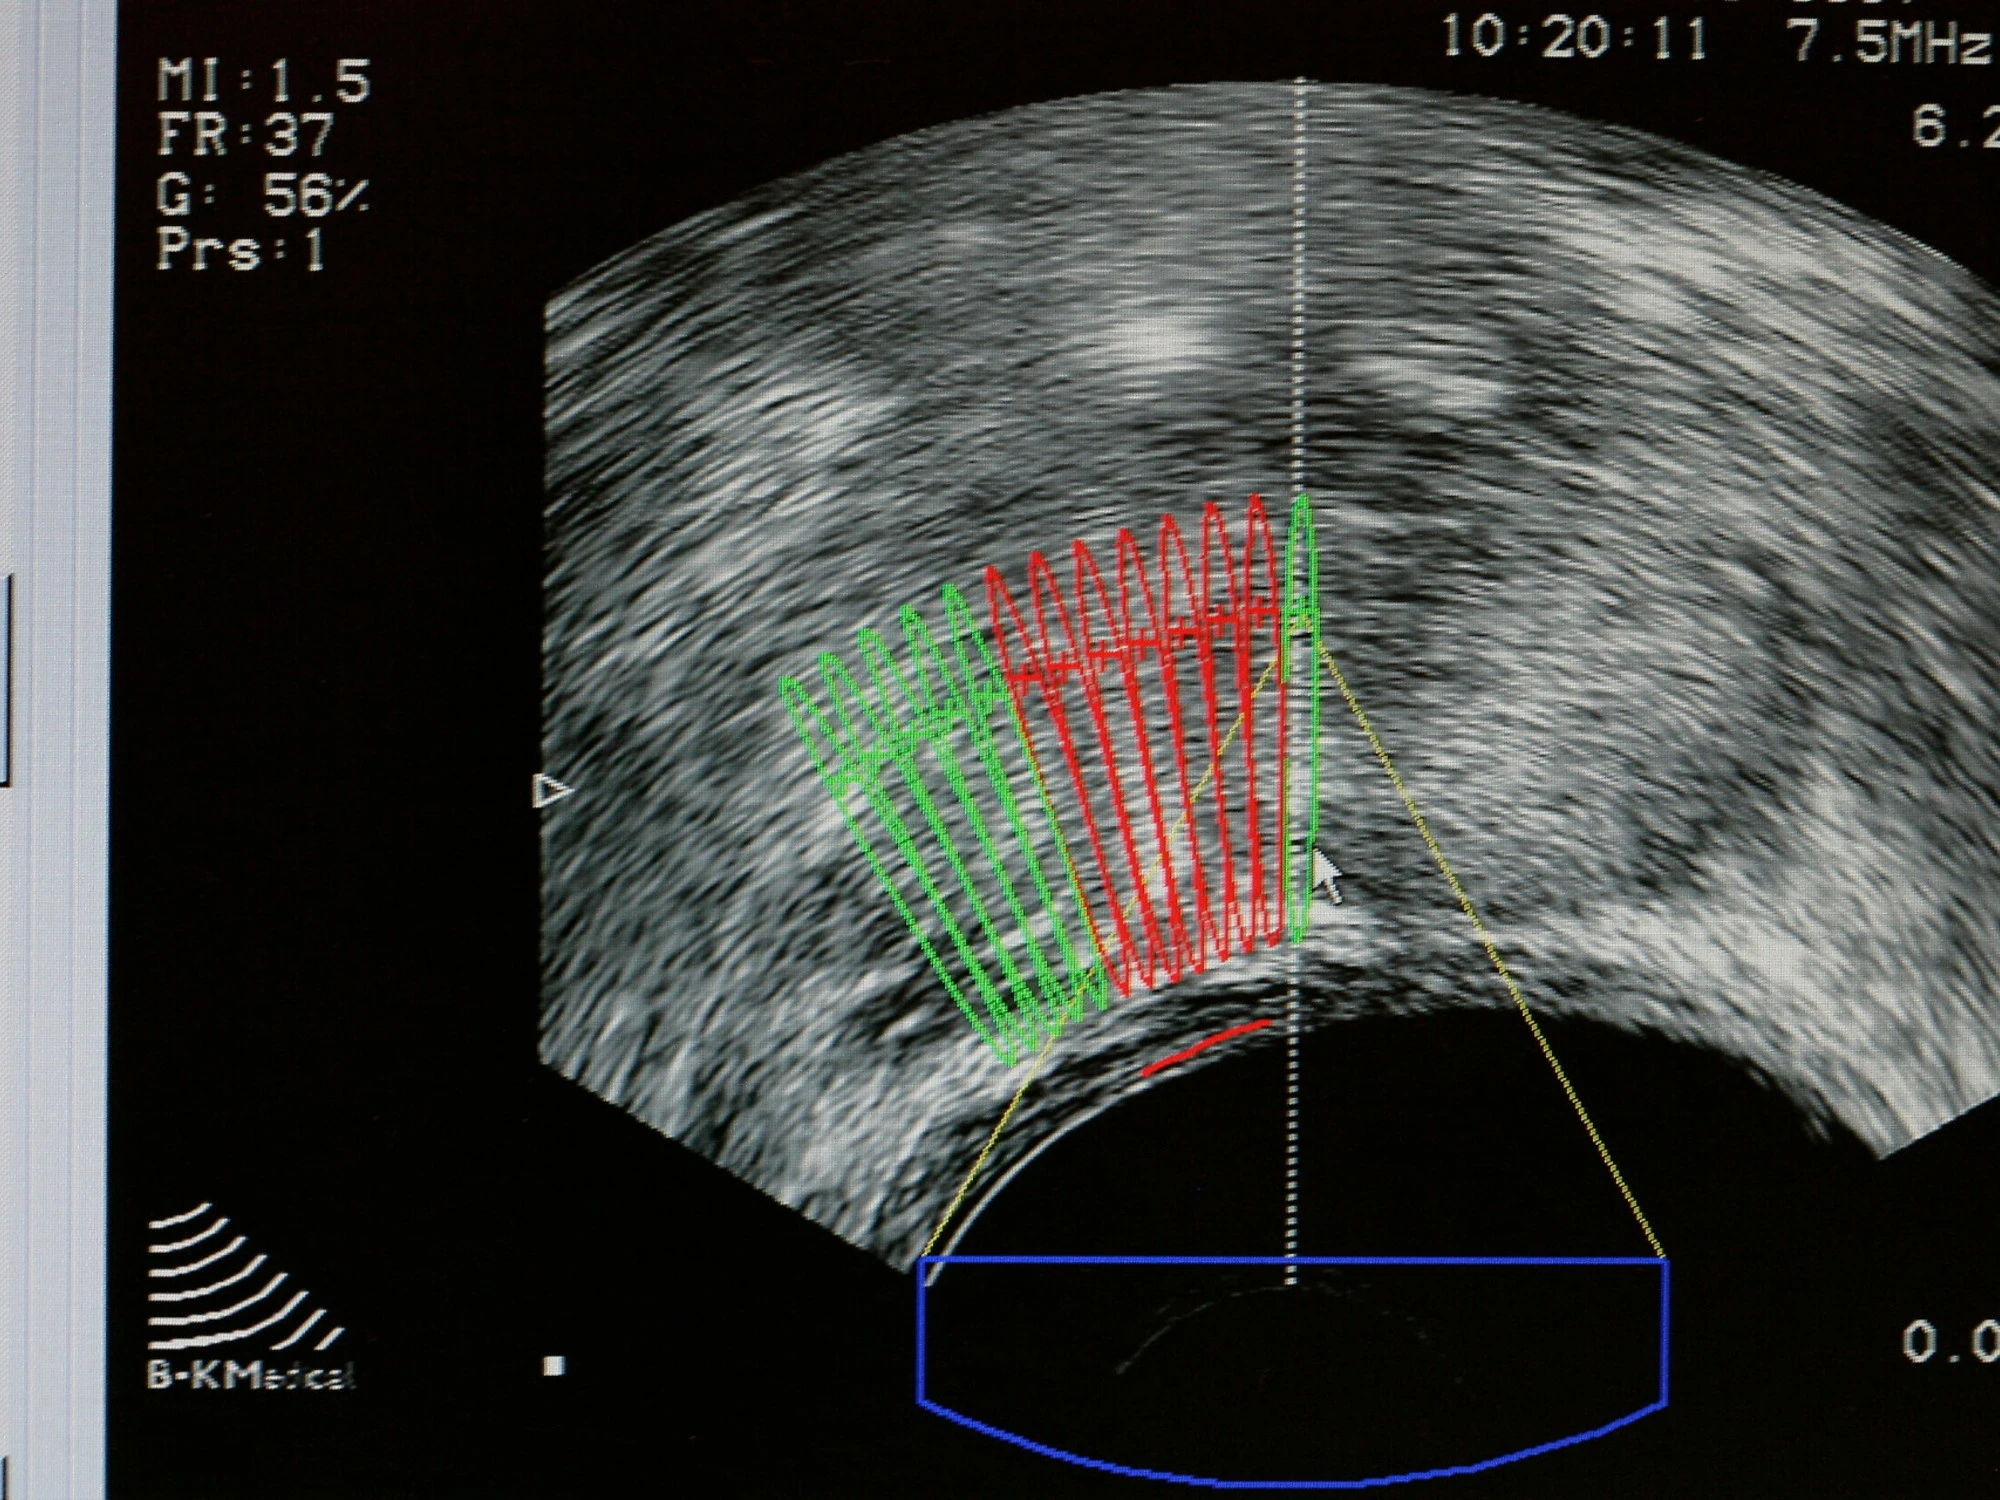

Il trattamento prevede appuntamenti rapidi, della durata di circa quindici minuti ciascuno, e rappresenta un importante passo avanti sia dal punto di vista clinico sia da quello organizzativo. La procedura non richiede interventi invasivi, non lascia radioattività residua nell’organismo e consente di somministrare dosi di radiazioni più elevate e altamente mirate. Tutto questo avviene mantenendo elevati standard di sicurezza e senza compromettere l’efficacia della cura, permettendo al paziente di tornare immediatamente alle proprie attività quotidiane.